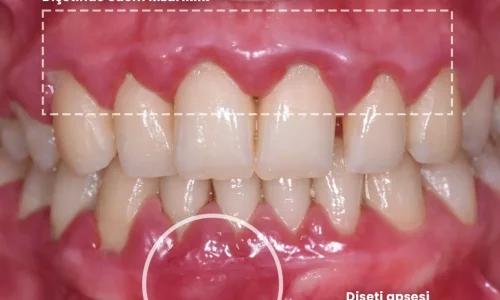

Diş Eti Hastalığı, Kanayan Diş Etleri ve Dişlerinizi Nasıl Kurtarırsınız

Diş eti hastalığı, kanayan diş etleri ve dişlerinizi nasıl koruyacağınız. Gingivitis ve ileri periodontitis belirtilerini öğrenin, etkili tedavi yöntemlerini keşfedin ve diş kaybını önlemek için atmanız gereken adımları anlayın.